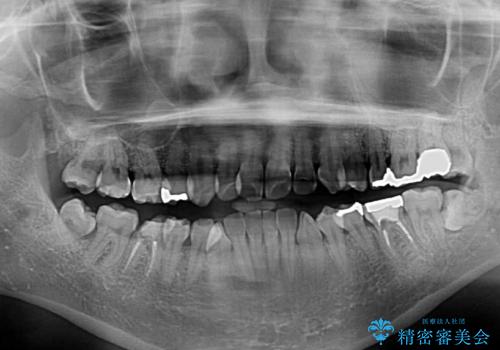

- 奥歯のむし歯を気にして来院された患者様です。

当初は右下の虫歯治療のみを希望されていましたが、虫歯治療に際して部分矯正が必要であったため、治療方法について説明をすると、全体的に歯列不正が気になっているとのことで、全顎矯正を検討することとなりました。

口元の突出感とデコボコがあり、上下左右の小臼歯4本を抜歯して矯正治療を行う方針としました。(右上は欠損のため計3本抜歯)

むし歯となっている歯は状態が悪く、将来的に抜歯となる可能性が高かったため、定石で抜歯させる小臼歯の代わりにむし歯となっている大臼歯を抜歯し、ワイヤー装置にて矯正治療を行うこととしました。